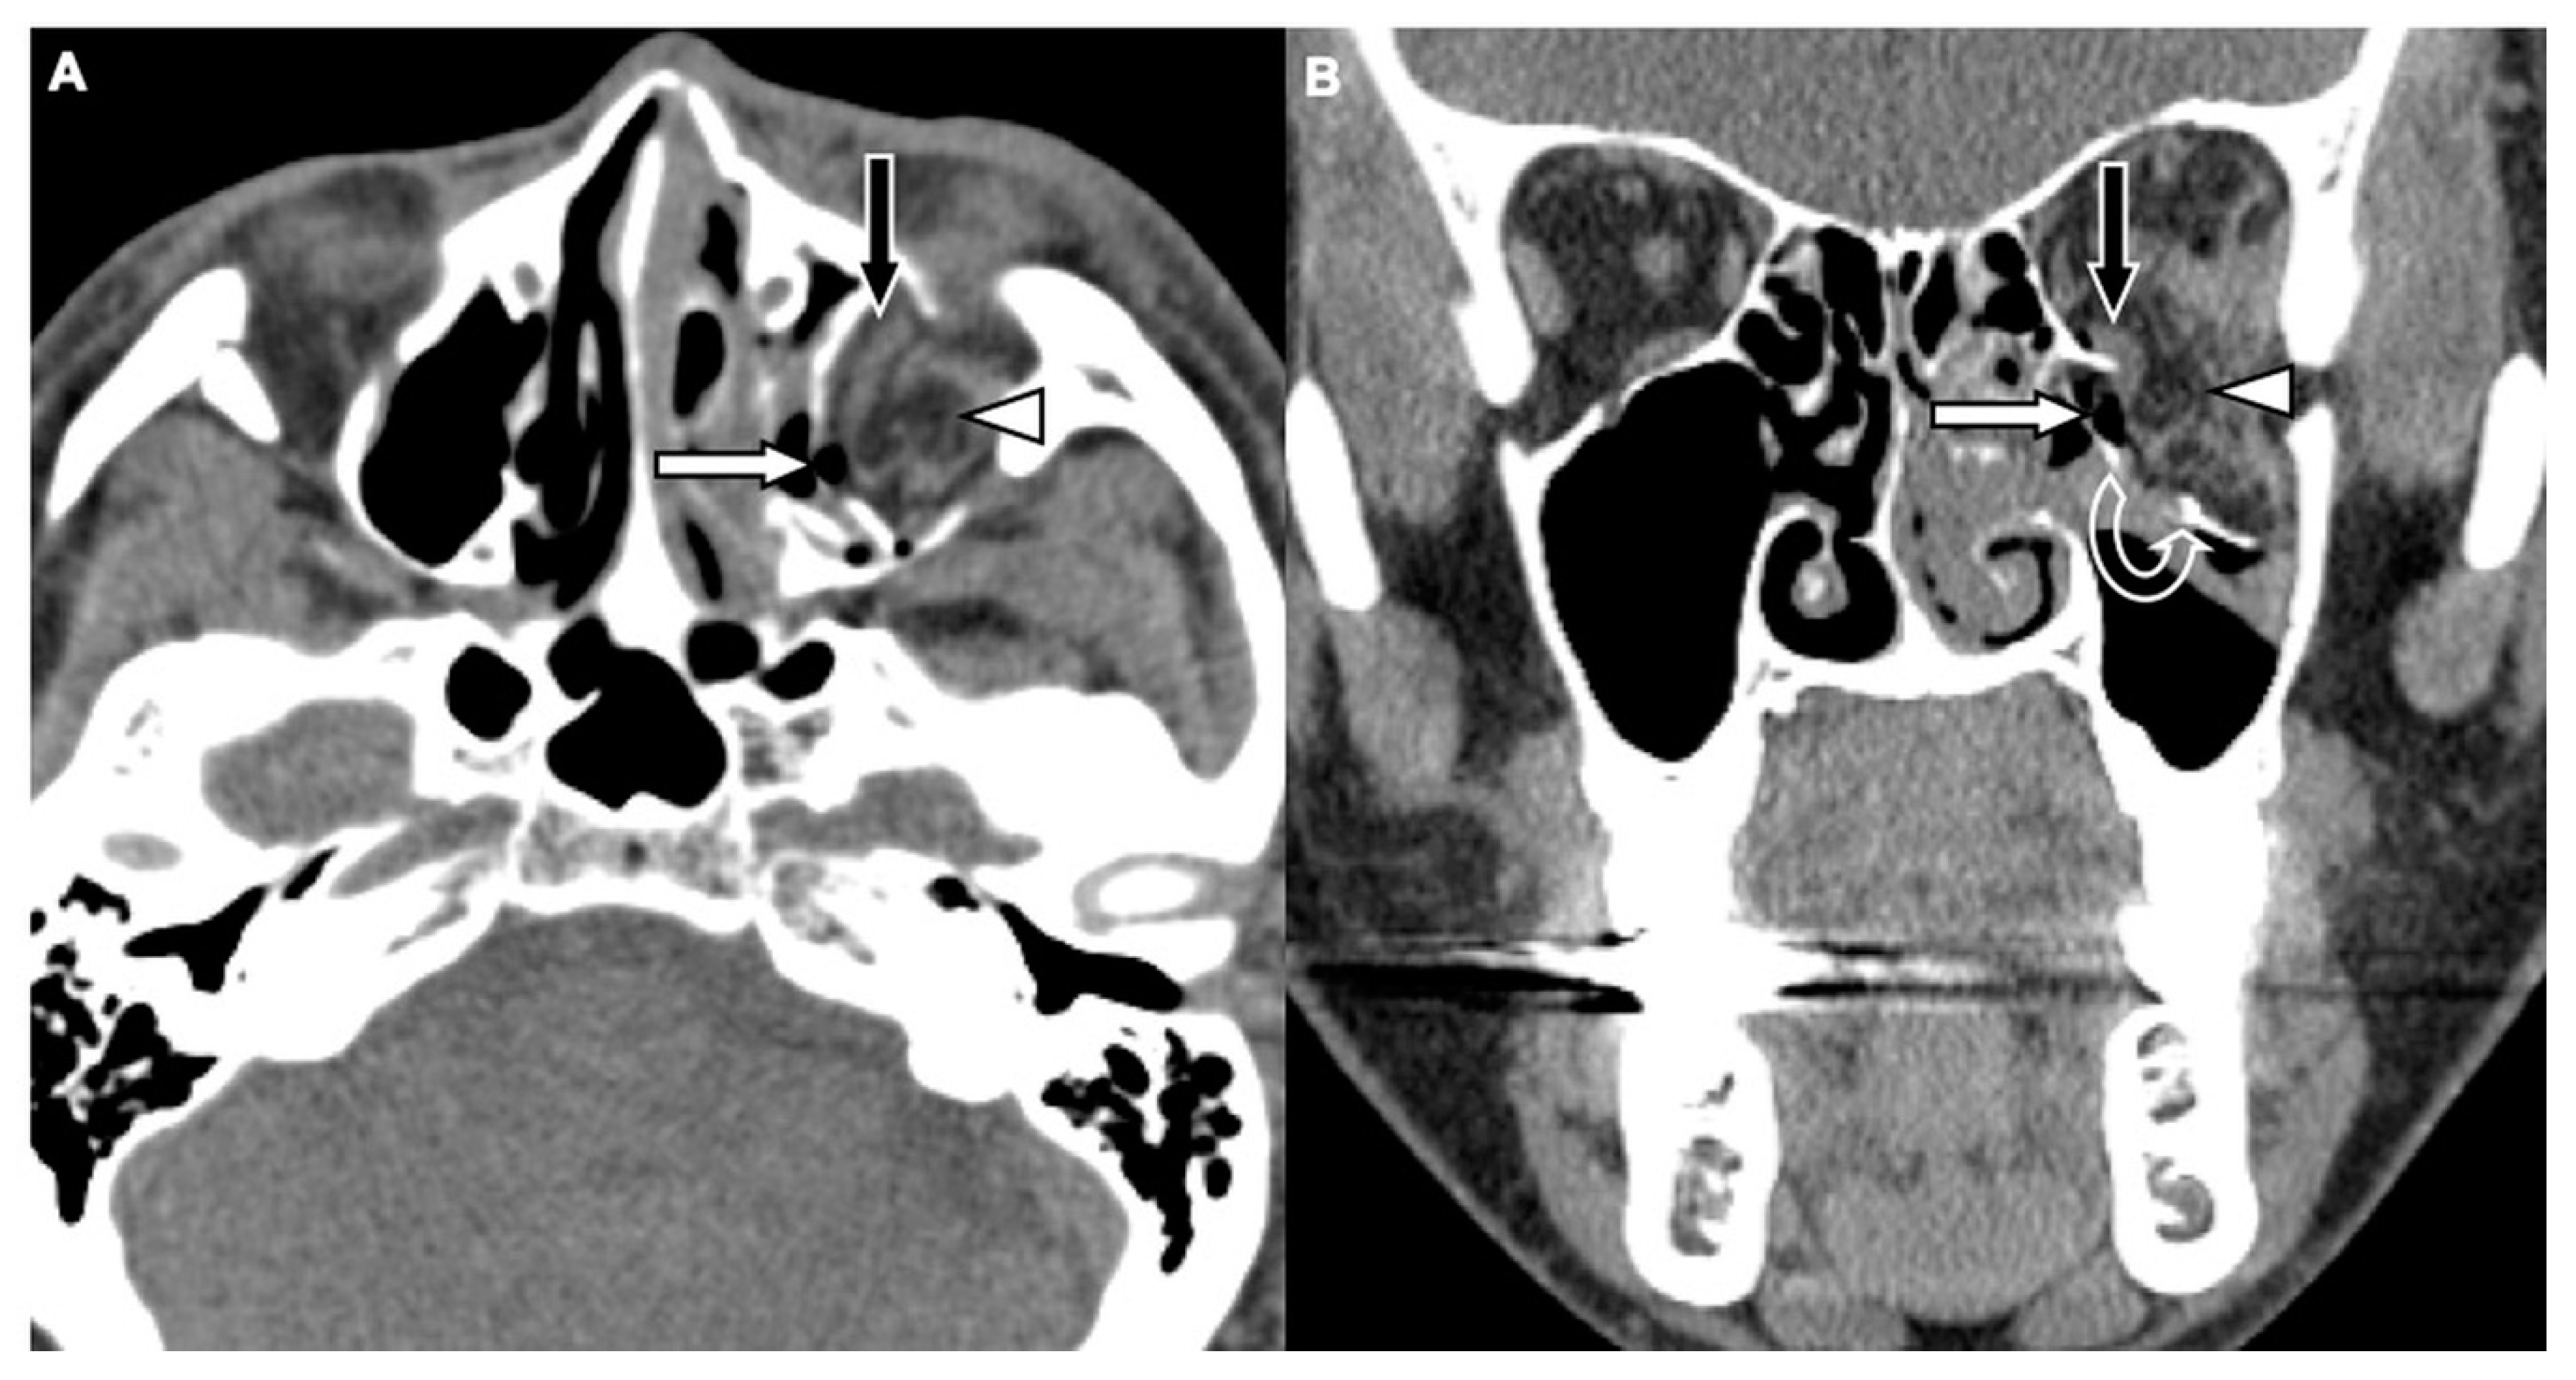

Two board-licensed radiologists (L.D.J. and Y.Y.C.) who were blinded to the patients’ clinical information reviewed only the head CT images by means of consensus. The radiologists were permitted to manipulate the window and level of the images. The CT variables related to the cranium included intracranial hemorrhage (ICH; epidural hemorrhage, subdural hemorrhage, subarachnoid hemorrhage, and intracerebral hemorrhage), and skull fractures. The CT variables related to OFFs included orbital floor discontinuity (Figure 1), gas bubbles entrapped between the floor fragments (Figure 1), inferior extraconal emphysema (Figure 2), orbital fat herniation into the maxillary sinus (Figure 2), and ipsilateral maxillary hemosinus (MHS, Figure 3). MHS was defined as high-attenuation opacity at the dependent portion of the maxillary sinus measuring ≥ 45 Hounsfield units (HU) as the lower limit of attenuation for clotted blood [15]. Since MHS is a relevant indicator used to detect OFFs on CT scans [5,16], we further classified MHS into the following three CT subtypes: (1) Type 1, high-attenuation opacity mixed with mottled gas (Figure 3A); (2) Type 2, air–fluid level (Figure 3B); and (3) Type 3, full opacification of the sinus (Figure 3C).

Figure 1. CT images of a 29-year-old male with assault-related head trauma and a concomitant left orbital floor fracture (OFF). An axial head CT image (A) and the corresponding coronal facial CT image (B) show gas bubbles (black arrow) entrapped between the discontinuous floor fragments (white arrows). Left type 2 maxillary hemosinus (MHS) (arrowhead) and a left zygomatic fracture are also noted in (A).